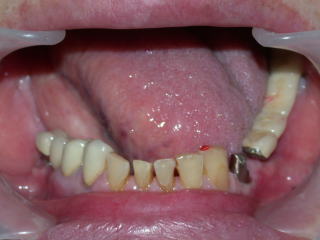

上部構造物装着です。

こちららの患者さんは他にインプラントを入れています。

「インプラントは費用がかかるが、それでも義歯よりとっても良い、義歯はとてもガマンできない。」そうです。